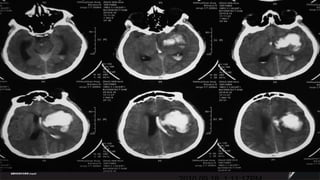

Case  Male ,47ys 2010.09.17  9:17PM Sudden onset of headache and hemiparalysis Muscle strength 0 degree, GCS11 .  BP180/120mmHg

2010.09.18  1:11:17PM

2010.09.18  6:07PM

2010.09.20  2pm

2010.09.25  9AM

2010.09.29  11AM

2010.10.07  12AM

2010.11.02  11AM

Case Male,47ys 2010.09.17 9:17PM Sudden onset of headache and hemiparalysis Muscle strength 0 degree, GCS11 . BP180/120mmHg